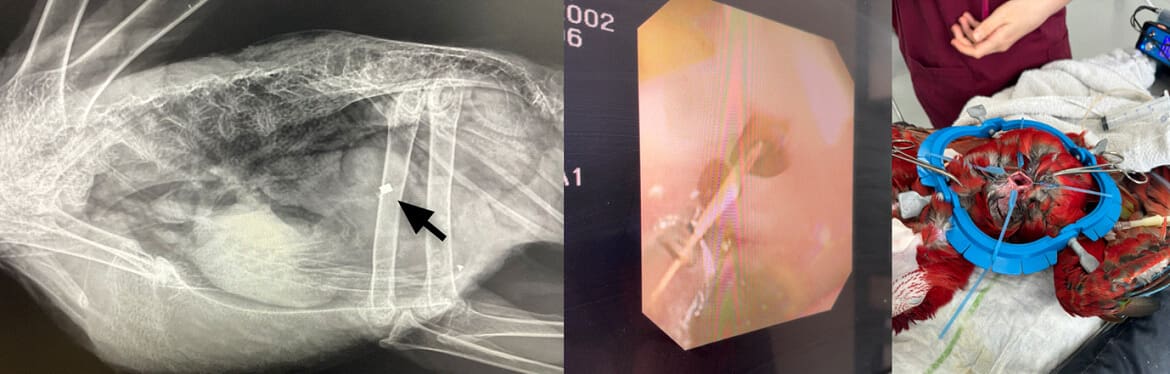

Princess, a 10 month old Scarlet Macaw, was seen by Dr. Ortiz following short episodes of lethargy, vomiting and diarrhoea. Radiographs showed evidence of a metal foreign body. Gastroscopy was performed using an ingluviotomy approach. After flushing large amounts of grit, seeds and feed out of the proventriculus a small square of copper was found in the ventriculus and successfully remove. Princess has made a great recovery and is her re-parrot proofed home!